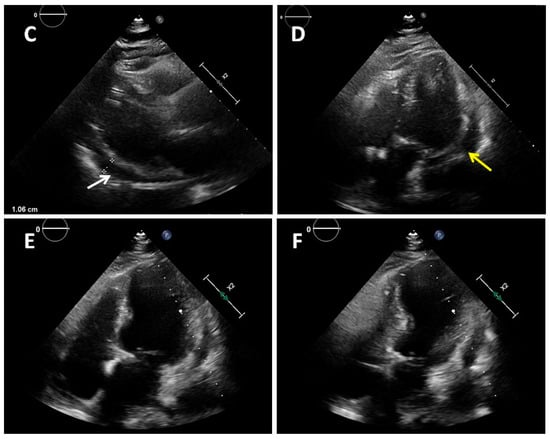

Figure 1. A 77-year-old obese woman with approximately 20 h of retrosternal pain was admitted to the clinic with suspected inferior STEMI infarction. The patient suffered from COVID-19 for four weeks before admission. On admission to the clinic, the patient reported chest pain. The ECG showed atrial fibrillation with a frequency of QRS about 100/min and ST-segment elevation in I, II, III, aVF, and V2-V6. The patient underwent coronary angiography, which revealed parochial atherosclerotic lesions in the coronary arteries (A,B) and, in the aortography, there were no signs of aortic dissection. The echocardiography showed normal valves function, good left ventricular systolic function with 58% ejection fraction (LVEF), and the presence of fluid in the pericardial sac, up to 10–11 mm behind the lower ((C), white arrow) and lateral ((D), yellow arrow) walls. The laboratory tests showed increased parameters of inflammation and normal levels of troponin and cardiac enzymes. Pericarditis was diagnosed and a treatment was started with colchicine, ibuprofen, enoxaparin, ceftriaxone, and levofloxacin. On the second day of hospitalization, the clinical condition of the patient deteriorated. There was an increase in renal parameters (creatinine—1.45 mg/dL, urea—100.5 mg/dL, and eGFR—37 mL/min) and atrial fibrillation with a fast QRS rate of 150/min. Pulmonary edema occurred, which was controlled by the intravenous infusion of furosemide and nitroglycerin. An echocardiogram was performed, which showed no significant changes. On the next day, the patient had a further deterioration in renal function with anuria. Hemodialysis was performed, followed by a return to diuresis. In the following days of hospitalization, the clinical condition of the patient improved. An echocardiographic examination was repeated in the patient every 1–2 days, confirming the good systolic function of the left ventricle and a constant amount of fluid in the pericardial sac. On the sixth day of hospitalization, the patient experienced a sudden cardiac arrest in the ventricular fibrillation (VF) mechanism. Resuscitation activities were undertaken, obtaining an atrial rhythm of about 90–100/min. In addition, the electrocardiogram showed a right bundle branch block and left bundle branch posterior bundle block (RBBB + LPH), QTc—510 ms. The patient was connected to a respirator and administered dobutamine, noradrenaline by continuous intravenous infusion, and amiodarone. The echocardiography revealed extensive abnormalities of contractility with akinesis of the apex, apical, and middle segments of all left ventricular walls, which may be consistent with Takotsubo syndrome (E,F). The ejection fraction was estimated at approximately 15%. There was a small amount of fluid in the pericardial sac. After a few hours, the patient returned to sudden cardiac arrest by VF and pulseless electrical activity (PEA). The resuscitation measures undertaken turned out to be ineffective, and the patient was pronounced dead. Patients with cardiovascular diseases are at risk of a severe course of COVID-19, as they are at risk of exacerbation of existing cardiological diseases and a higher risk of complications. Cardiological complications also often occur in COVID-19 patients with no previous history of cardiac diseases [1]. Pericarditis occurs in 3% of patients with COVID-19. The main symptom of pericarditis is retrosternal pain; ECGs show diffuse ST-segment elevations and echocardiography shows a small amount of fluid in the pericardial sac and elevated parameters of inflammation. The prognosis of patients is usually favorable [2]. The literature data on Takotsubo syndrome in COVID-19 is limited, but to date it has been noticed that a small percentage affects women, who constitute 50–60% of the groups of patients (90% before COVID-19). The more frequent stressor causing TS is the physical factor [3,4]. The diagnosis of Takotsubo syndrome in COVID-19 is significantly difficult and is often based on echocardiography and the probability of Takotsubo according to the InterTAK scale [5]. The prognosis of patients is unfavorable, and mortality is about 30–40%. Takotsubo syndrome with severe arrhythmias and acute heart failure was the direct cause of death of our patient. The patient’s condition required the use of inotropic drugs, which probably did not improve her prognosis. Currently, in TS with cardiogenic shock, the use of levosimendan is recommended and mechanical circulatory support should be considered (intra-aortic balloon pump, Impella or ECMO) [6,7]. Various cardiac complications in both acute COVID-19 and later post-COVID syndromes worsen the prognosis of these patients. The number of stress factors associated with falling ill with COVID-19 increases the risk of Takotsubo syndrome. The differences in Takotsubo syndrome in COVID-19, demonstrated to date, require confirmation in subsequent prospective studies and discussion on the verification of the criteria for diagnosing TS in patients with COVID-19.